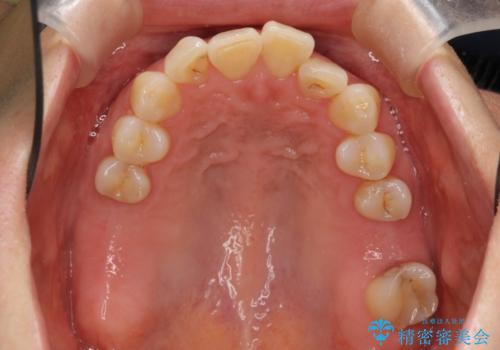

前歯が反対になっている マウスピース矯正+奥歯ブリッジ

- 前歯のがたつきを主訴に来院。

奥歯も少なく、左上奥歯はブリッジにすることになりました。

左下の前歯を中に入れるスペースを確保する目的で左下の奥歯を後ろ移動させました。

また、左下の小臼歯の捻転はマウスピースで治りにくいため、

事前にワイヤーによる部分矯正を行い、矯正用ミニスクリューを植立しています。